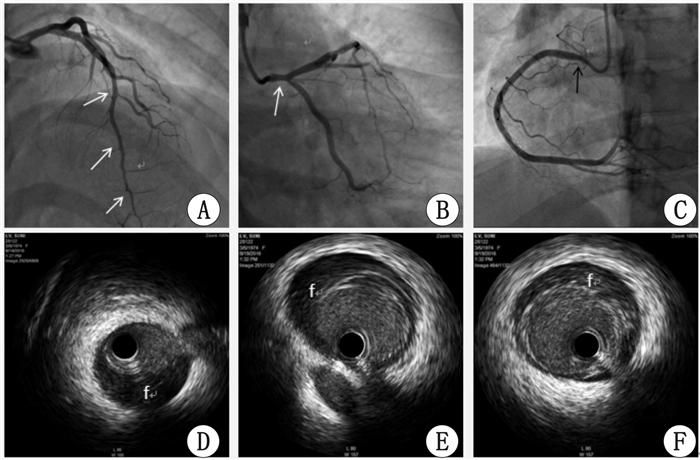

1 资料与方法病例1 患者,女,42岁,因“右冠支架植入术后5年余,再发胸痛1周”于2016年9月16日入院。2011年2月11日曾因“反复胸痛半月,晕厥2次”住本院。2011年1月26日因丧父悲痛后反复胸痛伴晕厥,当地卫生院予以输液时再发晕厥后转本院。入院后查心电图示:Ⅱ、Ⅲ、aVF导联T波倒置,胸主动脉CTA未见异常。2011年2月16日冠脉造影显示右冠开口、近段及中段弥漫性狭窄病变,右冠中段最重处近乎闭塞(图 1A、B)。右冠IVUS显示右冠近段及中段夹层,血肿延伸至右冠开口(图 1C)。诊断:自发性右冠冠状动脉夹层,急性非ST抬高性心肌梗死。行右冠植入4枚紫杉醇药物支架。术后服用拜阿司匹林、氯吡格雷、美托洛尔等药物,无再发胸痛。2016年9月8日无诱因下出现反复胸骨中上段胸痛,放射至左侧肩背部,每次持续20 min后自行缓解。入院查体:BP113/60 mmHg(1 mmHg=0.133kPa),神清,两肺呼吸音粗,心率80次/min,律齐。心肌酶:CK-MB 34 U/L(参考值2~25),肌钙蛋白I(TNI)3.115 pg/mL(参考值0.000~0.060)。心电图:Ⅱ、Ⅲ、aVF、V1~V6导联T波双向或倒置。诊断为:急性非ST抬高性心肌梗死,自发性右冠冠状动脉夹层,右冠支架植入术后。冠脉造影显示:左前降支中段至远段弥漫性狭窄最重80%狭窄,对角支开口75%狭窄,左回旋支开口70%狭窄,右冠开口原支架内70%狭窄(图 2A、B、C)。IVUS显示:右冠开口最小管腔面积2.91 mm2,左主干至左前降支远段全程夹层及壁内血肿形成,远段管腔重度狭窄,左回旋支开口重度狭窄、未见夹层及血肿(图 2D、E、F)。以紫杉醇药物球囊行右冠开口原支架内扩张术。继续予以抗血小板、扩冠等药物治疗,出院随访至今,无不适主诉。

| 图 2 病例1冠脉造影及IVUS(2016年9月19日):白色箭头示自发性夹层,黑色箭头示右冠开口重度狭窄,f示假腔;D图为左前降支远段、E图为左前降支开口、F图为左主干末端 |